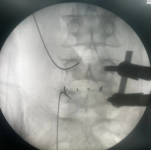

3.微创PKP技术:老年压缩性骨折球囊扩张椎体成形术

经皮球囊扩张椎体后凸成形术是好看视频下载

很早就开展的一项微创技术,已经有20多年,每年手术约200例,尤其适用于老年骨质疏松引起的胸腰椎骨折;椎体转移性肿瘤(溶骨性破坏);引起疼痛症状的椎体血管瘤、多发性骨髓瘤、Kummell 症。局部麻醉,创伤小恢复快,第二天可以下床活动,迄今为止最高手术患者92岁高龄。